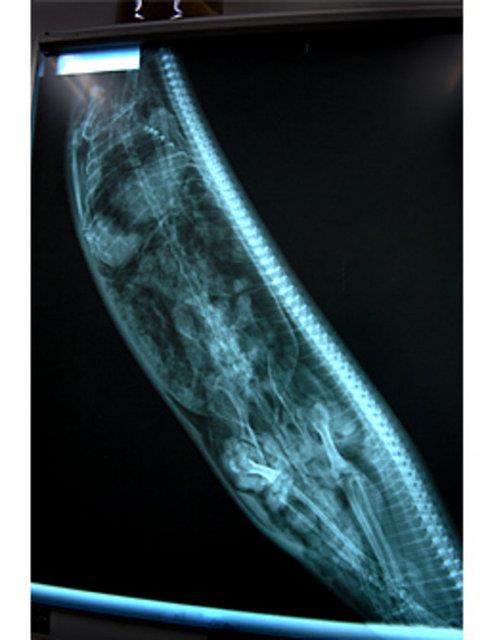

13. İki buçuk metre piton yılanın içinde ölü taklidi yapan bir yılan avcısı...

İki buçuk metre piton yılanın içinde ölü taklidi yapan bir yılan avcısı...